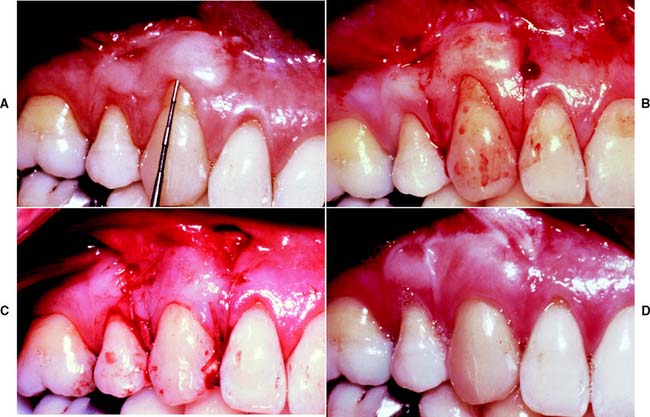

A free (detached) autogenous gingival graft (Fig. 6-13) is used to increase the width of attached gingiva in areas where it is deemed inadequate. The donor site most commonly used is the hard palate, although any area of keratinized tissues, such as an edentulous ridge or the retromolar pad, may be suitable.

Fig. 6-13 Free autogenous gingival graft. A, Planned abutment tooth lacking adequate keratinized gingiva. B, The recipient site is prepared. C, The graft is sutured to place. Some apical adjustment is needed around the premolar before application of the surgical dressing. D, The healed graft. (Compare the width of attached keratinized gingiva here with that in part A.) The defective restoration can be treated at this stage.

The recipient bed site is prepared by making a horizontal split-thickness incision just coronal to the mucogingival junction. As the incision passes apical to the junction, it may become either split thickness or full thickness.36,37 The recipient bed is trimmed of tissue tags and thinned. (A template of tinfoil may be used as a guide for the correct size and shape of the graft.) The graft is then carefully removed from the donor site, and any fat or glandular tissue is excised, so that a maximum thickness of 1 mm is left. Sterile saline is used to keep the graft moist until it is placed on the recipient bed for a check of size and shape, and it is then further shaped if necessary. When the proper dimensions have been attained, the graft is sutured into place. Finally, the graft site and the donor site may be covered with a surgical dressing. Complete healing requires approximately 6 weeks,38,39 at which time the donor site and the grafted site should appear normal.